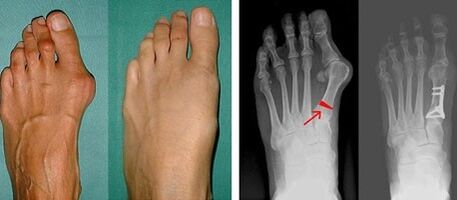

Valgus deformity of the first toe most often affects women of mature age, but it also affects men.The deformed base of the thumb does not look aesthetically pleasing.In this case, the person feels physical discomfort, and in the advanced stage - pain.The deviation of the big toe is the result of the uneven load of the body on the foot.Such changes have a detrimental effect on the feet and other toes.

In the first stage of identifying the valgus of the thumb and little finger, the doctor performs a visual examination.In this way, it determines the stage of development of the pathology.To identify detailed changes in the joint, x-rays and plantography are prescribed.

If the visual examination and radiography do not give any results, then the patient is directed to plantography to determine possible flat feet.This method involves taking prints of the feet, based on which shoes or insoles with orthopedic properties are made for the patient.The patient is then prescribed pedometry.This method uses computer analysis to determine the pressure of a person's weight on their feet.The results of advanced diagnostics are the basis for choosing a treatment method for the curvature of the first and second fingers.

The disadvantage of X-ray examination is the need to irradiate the patient's legs, which many patients do not like.They think this is a very harmful method.In this regard, the effective treatment of hallux valgus cannot be started without the results of plantography.